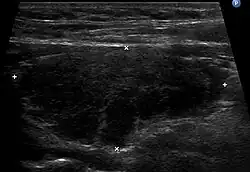

Imagerie

L'échographie de la thyroïde montre un goitre hypoéchogène[20],[18]. Le parenchyme thyroïdien devient plus hétérogène au cours de l'évolution. On peut notamment mettre en évidence des pseudo-nodules et des nodules de régénérations hyperéchogènes (white knight)[18]. Des ganglions récurrentiels peuvent être visualisés[18]. La vascularisation est hétérogène en Doppler couleur. L'étude en Doppler pulsé retrouve une élévation des vitesses systoliques[18], toutefois moindre que dans la maladie de Basedow.